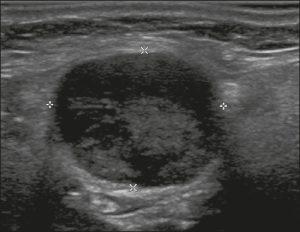

Hình 19. Hình ảnh nhân giáp dạng đặc (2 điểm), giảm âm rất mạnh (3 điểm), rộng hơn cao (0 điểm), có bờ trơn láng (0 điểm), và không có các ổ tăng âm hay bóng lưng (0 điểm). Do đó, tổng điểm là 5 điểm và mức độ nguy cơ được phân loại là TR4.